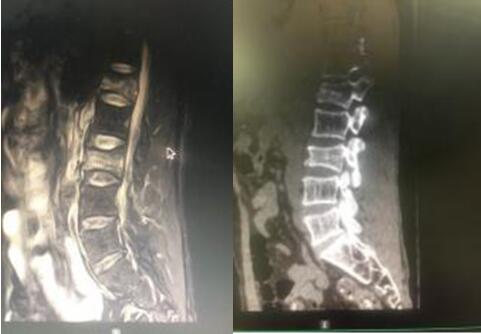

7月9日,經與患者及其家屬充分溝通后,在脊柱外科蘇光輝主任、汪向東副主任帶領下順利進行了經皮跨傷椎長節(jié)段后路內固定手術治療腰椎骨折。術后傷口小、出血量極小約50ml,術后1周即可下地行走,患者及其家屬對手術效果相當滿意。

術后